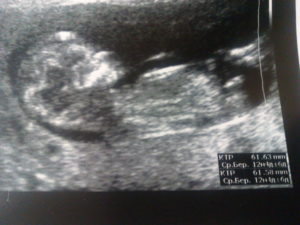

Фотогалерея

Снимок девочки, около 12 недель Снимок двойни Фото на УЗИ, девочка Фото на УЗИ, мальчик Снимок мальчика, 12 недель Разница в снимках УЗИ мальчика и девочки

В 12 недель беременности фото плода покажет вам, как вырос малыш. Это будет первым снимком ребенка.

Именно с этого периода начинаются самые интересные и удивительные перемены: малыш усиленно растет, функции всех его органов совершенствуются для того, чтобы потом после рождения быстрее акклиматизироваться к новым условиям обитания вне живота. В 12 недель беременности фото плода на УЗИ покажет вам ребенка, который значительно вырос с момента зачатия.

12 недель беременности размер плода фото УЗИ

Практически всех будущих мам интересует, что же происходит с их ребенком на данном сроке. Размер плода около 8 сантиметров, а его вес около 18-22 грамм. Основные внутренние органы практически сформированы, а все остальные крайне быстро развиваются.

Фото УЗИ 12 недель беременности

Фото УЗИ на 12 неделе беременности